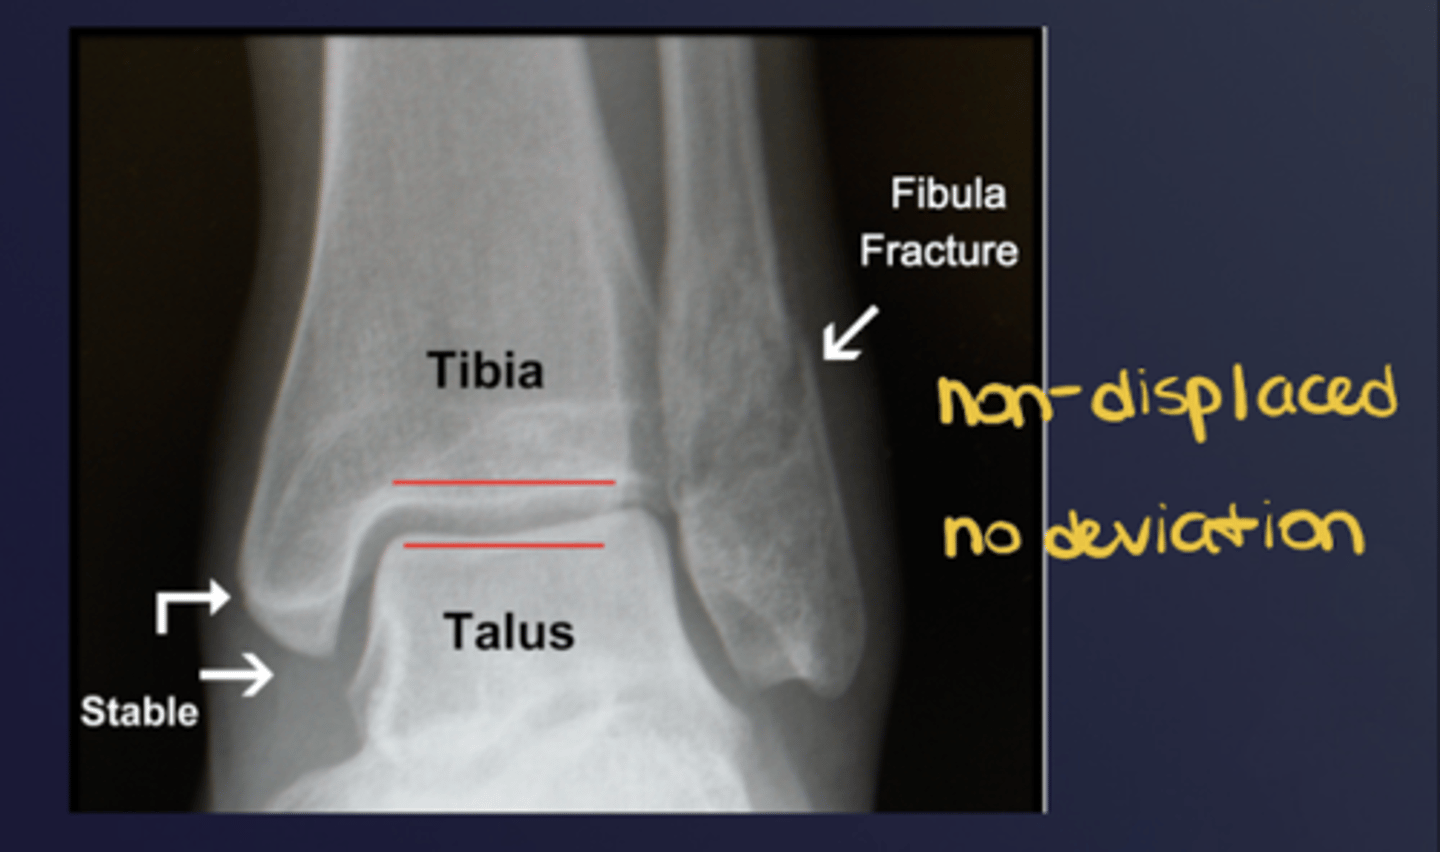

What is the position of fragments (under #3 "relationship of fragments")? What is an abnormality known as?

Degree of apposition at osseous ends; abnormality = displacement

What is the alignment of fragments (under #3 "relationship of fragments)? What is an abnormality known as?

Angular relationship; one fragment to another; abnormality = deviation

What does good position, good alignment look like vs. displaced with deviated alignment?

See image.